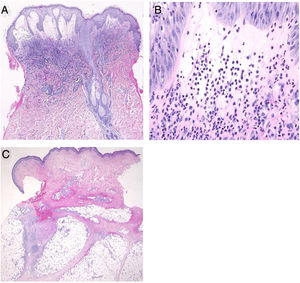

(A), Características histológicas mostrando densa infiltração de neutrófilos em toda a derme edematosa (Hematoxilina & eosina, aumento original 40×). (B), Um aumento maior mostrou vários neutrófilos infiltrados (Hematoxilina & eosina, 400×). (C), Exame histológico do nódulo subcutâneo da extremidade inferior mostrando paniculite septal (Hematoxilina & eosina, 20×).

O exame laboratorial mostrou contagem de leucócitos de 8.100/μL com 3% de bastonetes, 21% segmentados, 9% linfócitos, 7% monócitos e 57% blastócitos, níveis diminuídos de hemoglobina (8,6g/dL) e plaquetas (108.000/μL), e níveis aumentados de proteína C reativa (26,02mg/dL). A hemocultura era estéril. Uma amostra de biópsia da borda periférica de bolha no pescoço mostrou bolha subepidérmica e infiltração neutrofílica densa na derme superior e média (fig. 2 A e B). A infiltração de células mieloides imaturas não foi detectada. Não foi observada infiltração de histiócitos/células histiocitoides, e o exame imuno‐histológico mostrou que as células CD68 e MPO‐positivas estavam espalhadas mas não eram proeminentes. Além disso, outra biópsia da parte inferior da perna mostrou infiltração de células inflamatórias, principalmente linfócitos, ao redor dos vasos no septo do tecido adiposo subcutâneo (fig. 2C). O exame hematológico e a biópsia da medula óssea revelaram a transformação da SMD em leucemia mielocítica aguda; imediatamente foi iniciada quimioterapia incluindo prednisolona. Após cerca de uma semana, todas as erupções bolhosas foram epitelizadas.